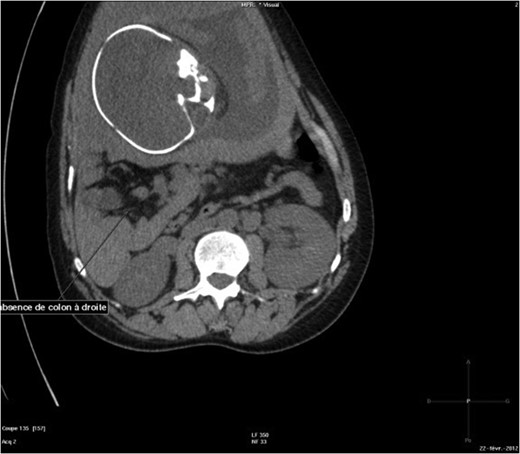

The abdominal-pelvic CT-scan showed a pre-splenic left position of the caecum and right colon, with no part of the colon on the right. The radiologist concluded that the patient was suffering from a complication of intestinal malrotation (IM) (Figs 1, 2, 3).

Abdominal-Pelvic CT-scan, non-contrast enhanced, in the sagittal plan, eleventh dorsal vertebra level.